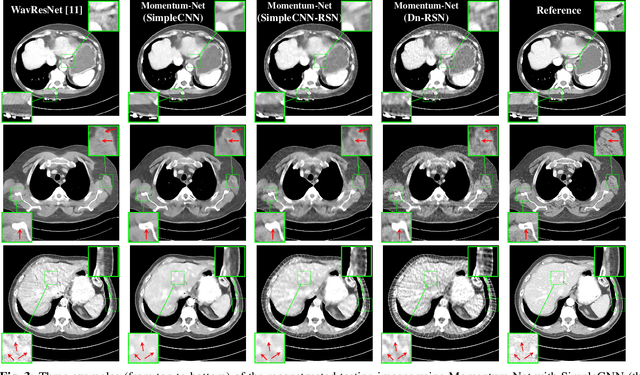

Abstract:This paper applies the recent fast iterative neural network framework, Momentum-Net, using appropriate models to low-dose X-ray computed tomography (LDCT) image reconstruction. At each layer of the proposed Momentum-Net, the model-based image reconstruction module solves the majorized penalized weighted least-square problem, and the image refining module uses a four-layer convolutional autoencoder. Experimental results with the NIH AAPM-Mayo Clinic Low Dose CT Grand Challenge dataset show that the proposed Momentum-Net architecture significantly improves image reconstruction accuracy, compared to a state-of-the-art noniterative image denoising deep neural network (NN), WavResNet (in LDCT). We also investigated the spectral normalization technique that applies to image refining NN learning to satisfy the nonexpansive NN property; however, experimental results show that this does not improve the image reconstruction performance of Momentum-Net.